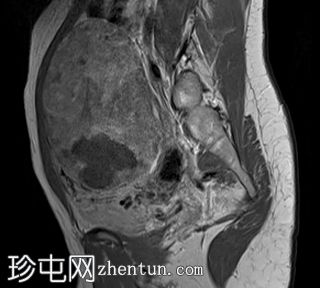

6.jpeg

矢状面

T2

子宫后壁可见一个边界清晰、体积较大的浆膜下肌瘤,大小约为16.1 x 10.5 x 14.4 cm(宽 x 深 x 高)。

该肌瘤在T1加权像上呈中等信号,在T2加权像上呈低信号,内部区域呈囊性变性。

该肿块导致正常子宫结构严重变形。增强扫描显示轻度不均匀强化,未见弥散受限征象或提示恶性肿瘤的可疑强化。

此外,子宫后壁可见多个小型子宫肌瘤,位于肌壁内和浆膜下,无任何退化征象。

双侧卵巢增大,各有超过10个卵泡,呈珍珠串状排列,周围未见优势卵泡。这些发现符合多囊卵巢的形态学特征。